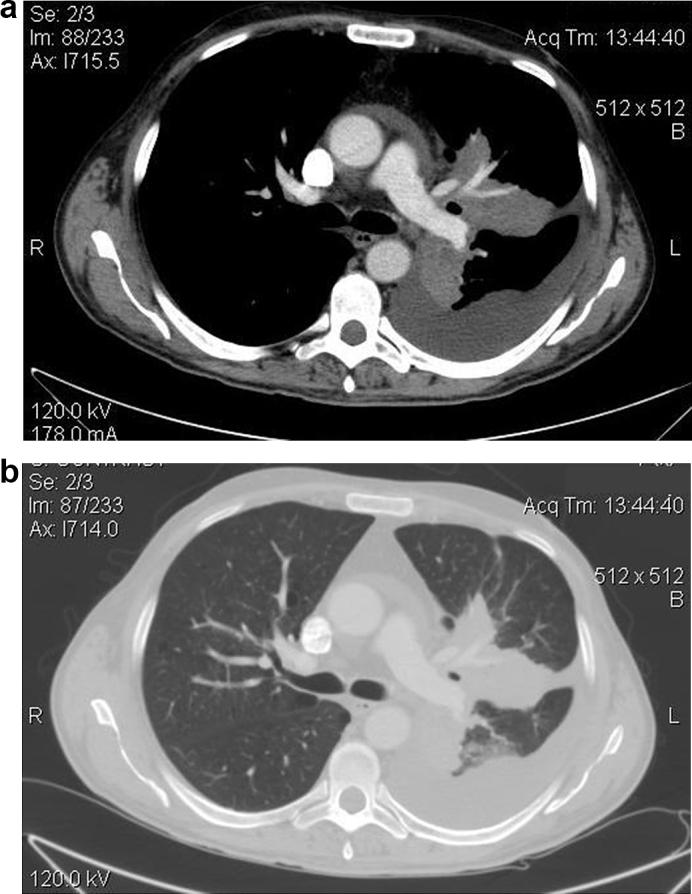

A 48-year-old man with prolonged fever and nausea was admitted to our hospital. Clinical examination revealed pathological auscultatory sounds to the left lung. Computed tomography was performed and revealed a large solid mass of the left upper lobe, limited pleural and pericardial effusion and calcified lymphadenopathy of mediastinum. A computed tomography guided core biopsy of the lung lesion was performed and three samples were obtained. Culture and polymerase chain reaction (PCR) revealed . Histological findings were compatible with bronchocentric granulomatosis. Extended laboratory investigation excluded immunosuppresion. Our patient although immunocompetent was diagnosed with chronic pulmonary histoplasmosis complicated with bronchocentric granulomatosis and treatment with antifungal medication and methylprednisoline started.

Description of a rare case of chronic pulmonary histoplasmosis in a non endemic area like Greece, with atypical radiological findings, complicated with bronchocentric granulomatosis.

一名48岁长期发热、恶心的男性入住我院。临床检查发现左肺有病理听诊音。进行了计算机断层扫描,显示左上叶有一个大的实性肿块、局限性胸腔和心包积液以及纵隔钙化淋巴结病。对肺部病变进行了计算机断层扫描引导下的芯针活检,获取了三个样本。培养和聚合酶链反应(PCR)显示……组织学结果与支气管中心性肉芽肿相符。进一步的实验室检查排除了免疫抑制。我们的患者虽然免疫功能正常,但被诊断为慢性肺组织胞浆菌病合并支气管中心性肉芽肿,并开始使用抗真菌药物和甲泼尼龙进行治疗。

描述了在希腊这样的非流行地区发生的一例罕见的慢性肺组织胞浆菌病病例,具有非典型的放射学表现,并合并支气管中心性肉芽肿。